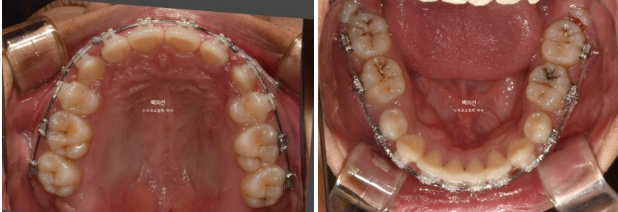

클리피씨 브라켓을 뗀 후 잇몸성형 직후 사진입니다.

앞니 각도와 어금니 교합은 좋고 1급 교합관계를 보입니다.

잇몸성형 일주일 후 잇몸이 잘 아물었습니다.